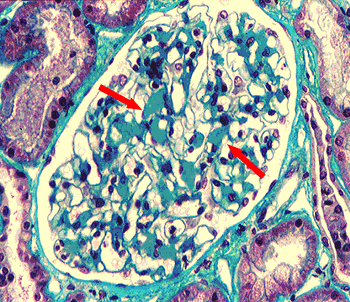

Това е рядко заболяване, което обикновено има фатален край; то се дължи на отлагането на патологичен белтък, наречен амилоид, в тъканите и органите на организма, който най-често се продуцира от клетките на костния мозък; постепенно протеинът води до увреждане функциите на органите, в които се натрупва; съществуват различни разновидности амилоид, които се отличават по някои оцветителни характеристики; съществуват три основни типа амилоидоза:

- вторична- този вид амилоидоза възниква най-често на базата на подлежащо хронично възпалително заболяване като туберкулоза, ревматоиден артрит, остеомиелит; тук могат да се засегнат всички тъкани и органи, но най-често страдат бъбреците, черният дроб, далакът и лимфните възли; в този случай лечението на първичното заболяване, довело до патологичното натрупване на амилоид в клетките на организма, може да предотврати по-нататъшната еволюция на амилоидозата.